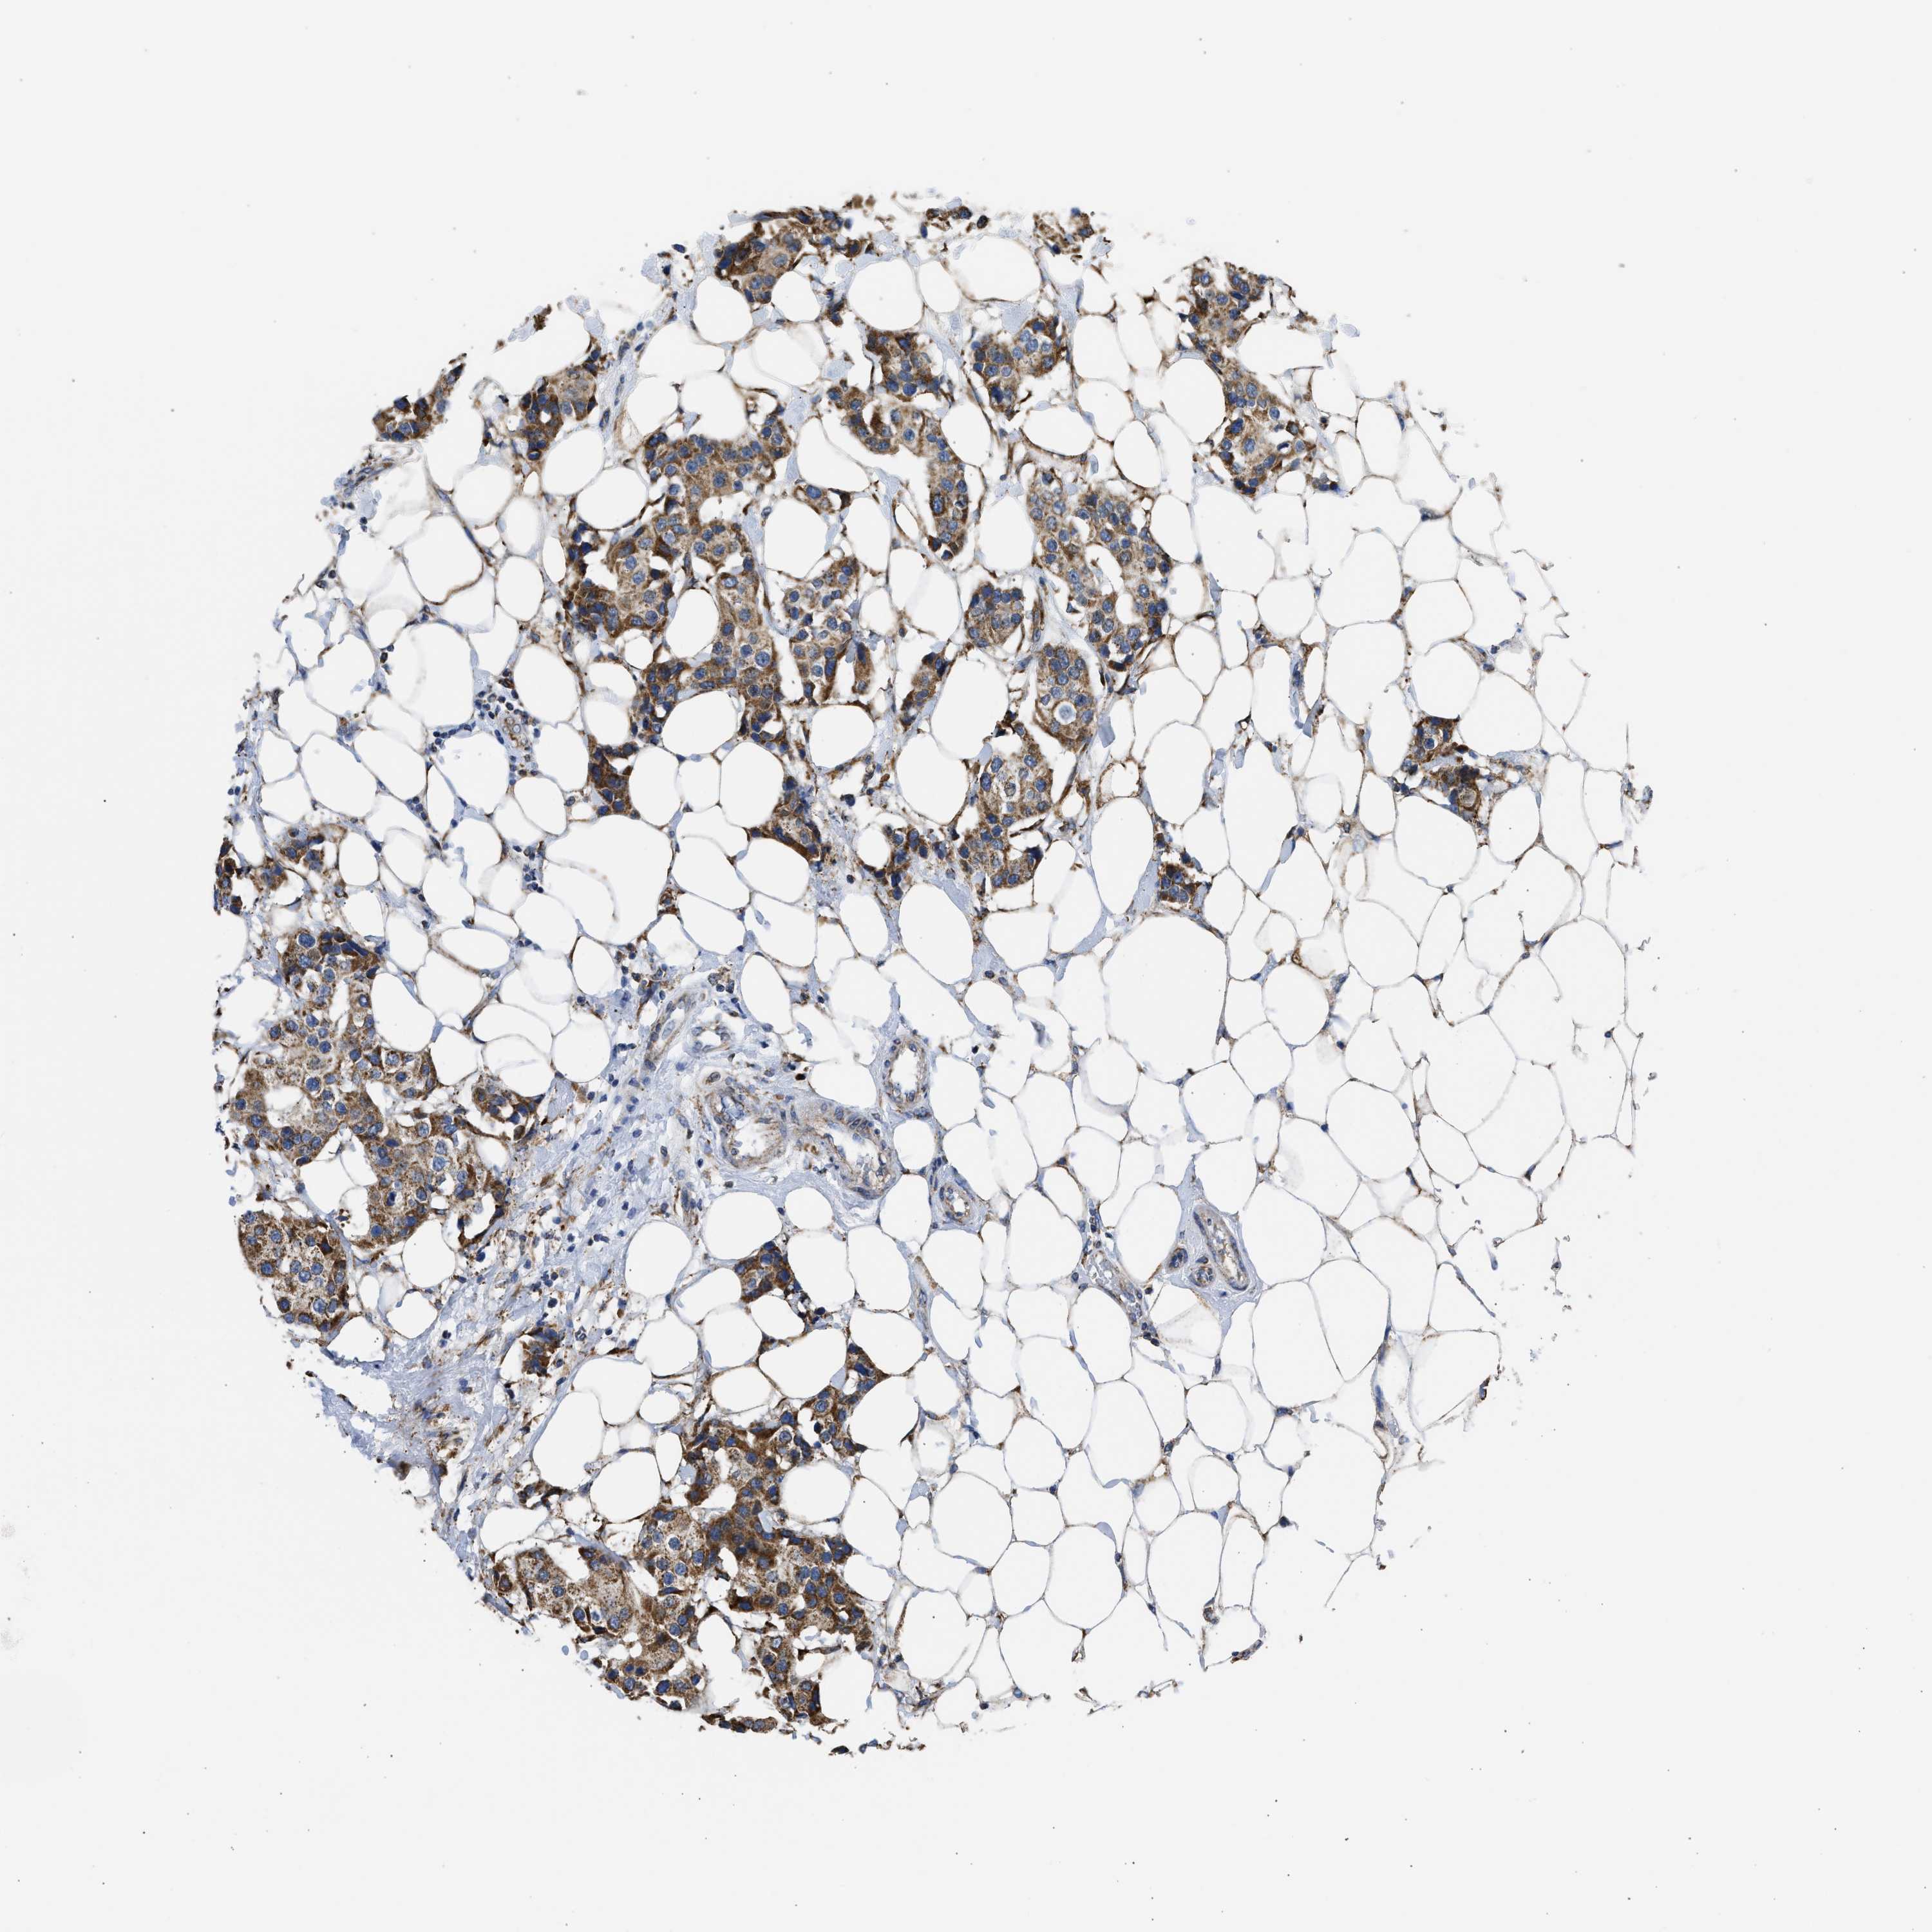

CANCER BREAST CANCER Show tissue menu

BRCA TCGA BRCA VALIDATION PROTEIN EXPRESSION